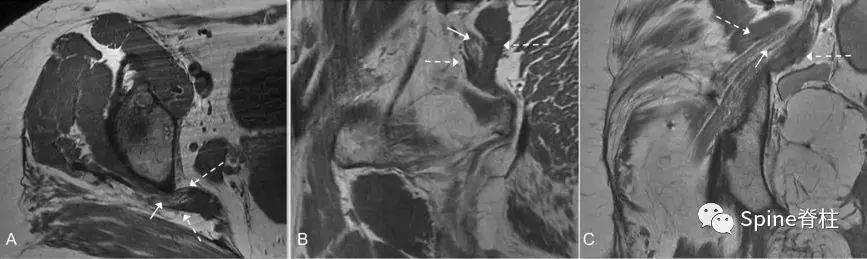

图示:MRI T1像的 Beaton-Anson 3型 。坐骨神经的腓总神经部分(白色细箭头)在梨状肌的后面(白色虚线箭头),胫神经部分(白色粗箭头)在前面。轴位(A)、矢状位(B)和冠状位(C)平面。

图示:MRI T1像的 Beaton-Anson 4型 。坐骨神经(细箭头)穿过梨状肌(虚线箭头)走行。轴位(A)、矢状位(B)和冠状位(C)平面。